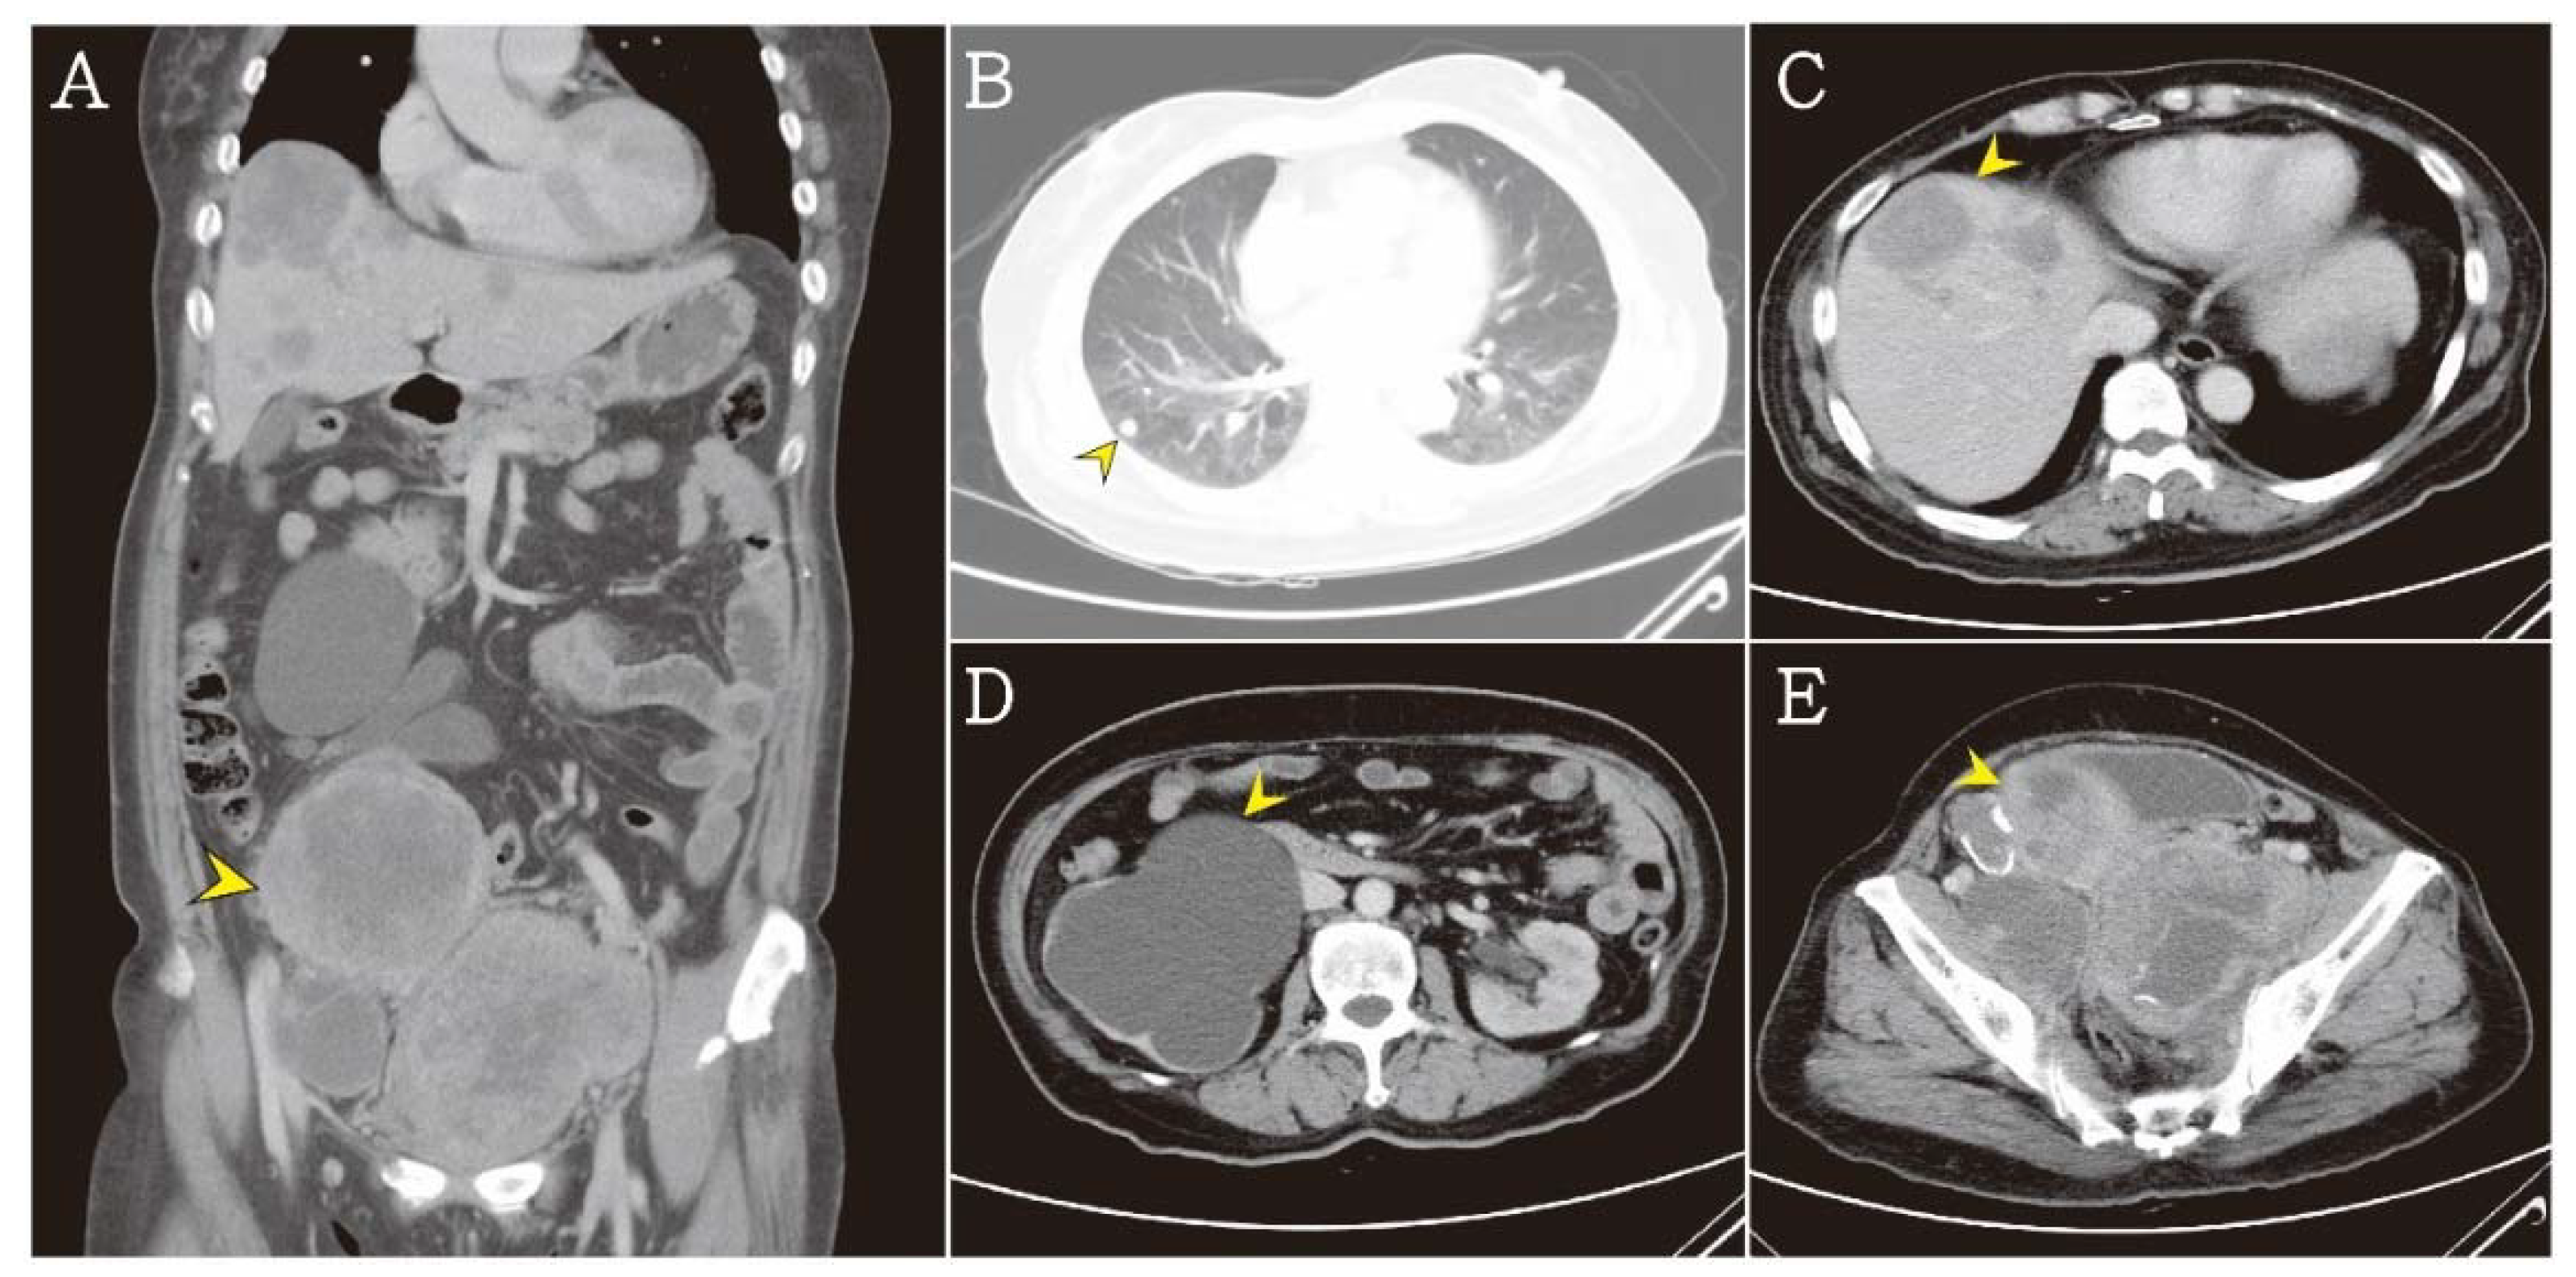

2. Case Presentation